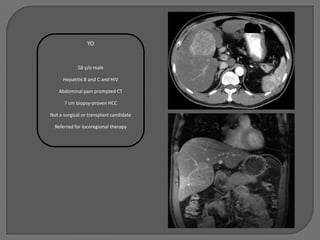

YO

58 y/o male

Hepatitis B and C and HIV

Abdominal pain prompted CT

7 cm biopsy-proven HCC

Not a surgical or transplant candidate

Referred for locoregional therapy